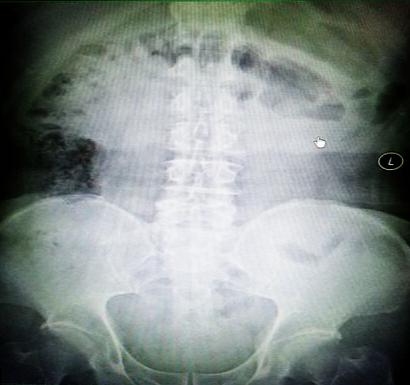

受試患者在結腸端端吻合術中,使用我司新研制產(chǎn)品達到了理想的預期效果。患者術后7天、14X光片顯影,可降解腸道支架均能按研制設計的預期時間節(jié)點保持應有強度,術后21X光片顯示可降解腸道支架已完全破碎,并排出體外。在整個試驗過程中,病患無任何不良反映,耐受良好。